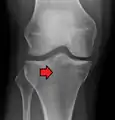

Lipohemarthrosis (presence of fat and blood from bone marrow in the joint space after an intraarticular fracture) seen on X-ray in a person with a subtle tibial plateau fracture

Lipohemarthrosis due to a tibial plateau fracture